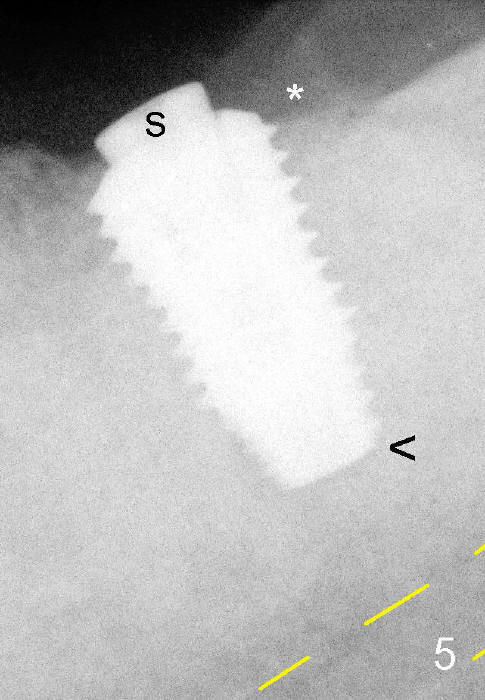

Since the ridge is wide, an extra wide implant is placed (Fig.2: 5.9x10 mm with insertion torque >55 Ncm) with one distal thread exposed (<). ^^: apical gap, which will be closed by further implant torquing (as compared to Fig.5 <).

The remaining distal exposed thread is covered by autogenous bone harvested during osteotomy (*).  The graft is then covered by collagen dressing, which is held in place by a partially placed healing screw (S).   There is clearance from the Inferior Alveolar Canal (yellow dashed line).